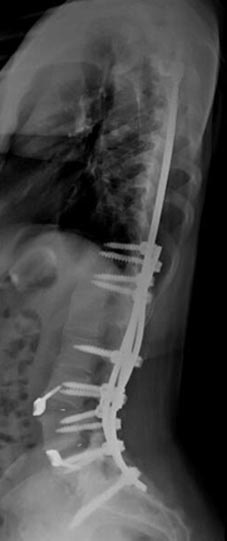

72 year old female who previously had a fusion with another surgeon who developed an infection and underwent multiple surgeries presenting with severe back pain with inability to stand upright.

46 year old woman who previously had Harrington rod spinal fusion from T4 to L3 for idiopathic adolescent scoliosis who presents with back pain and left leg weakness from severe lumbar stenosis distal to her previous fusion.

3 months postop, patient is pain free and weakness completely resolved. She is able to stand upright without pain and improved posture.